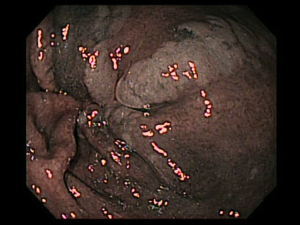

Detección endoscópica de las condiciones precancerosas

El uso de la endoscopia de luz blanca de alta resolución con una cromoendoscopia es de mucha utilidad y mucho mejor teniendo una precisión diagnóstica del 88% y una especificidad del 94% y una sensibilidad del 74,6% siendo esta la más utilizada, la toma de biopsias según sydney tenían precisiones diagnósticas de atrofia y metaplacia en un 93 y 90%, entonces esto sería de mucha utilidad para un diagnóstico precanceroso.